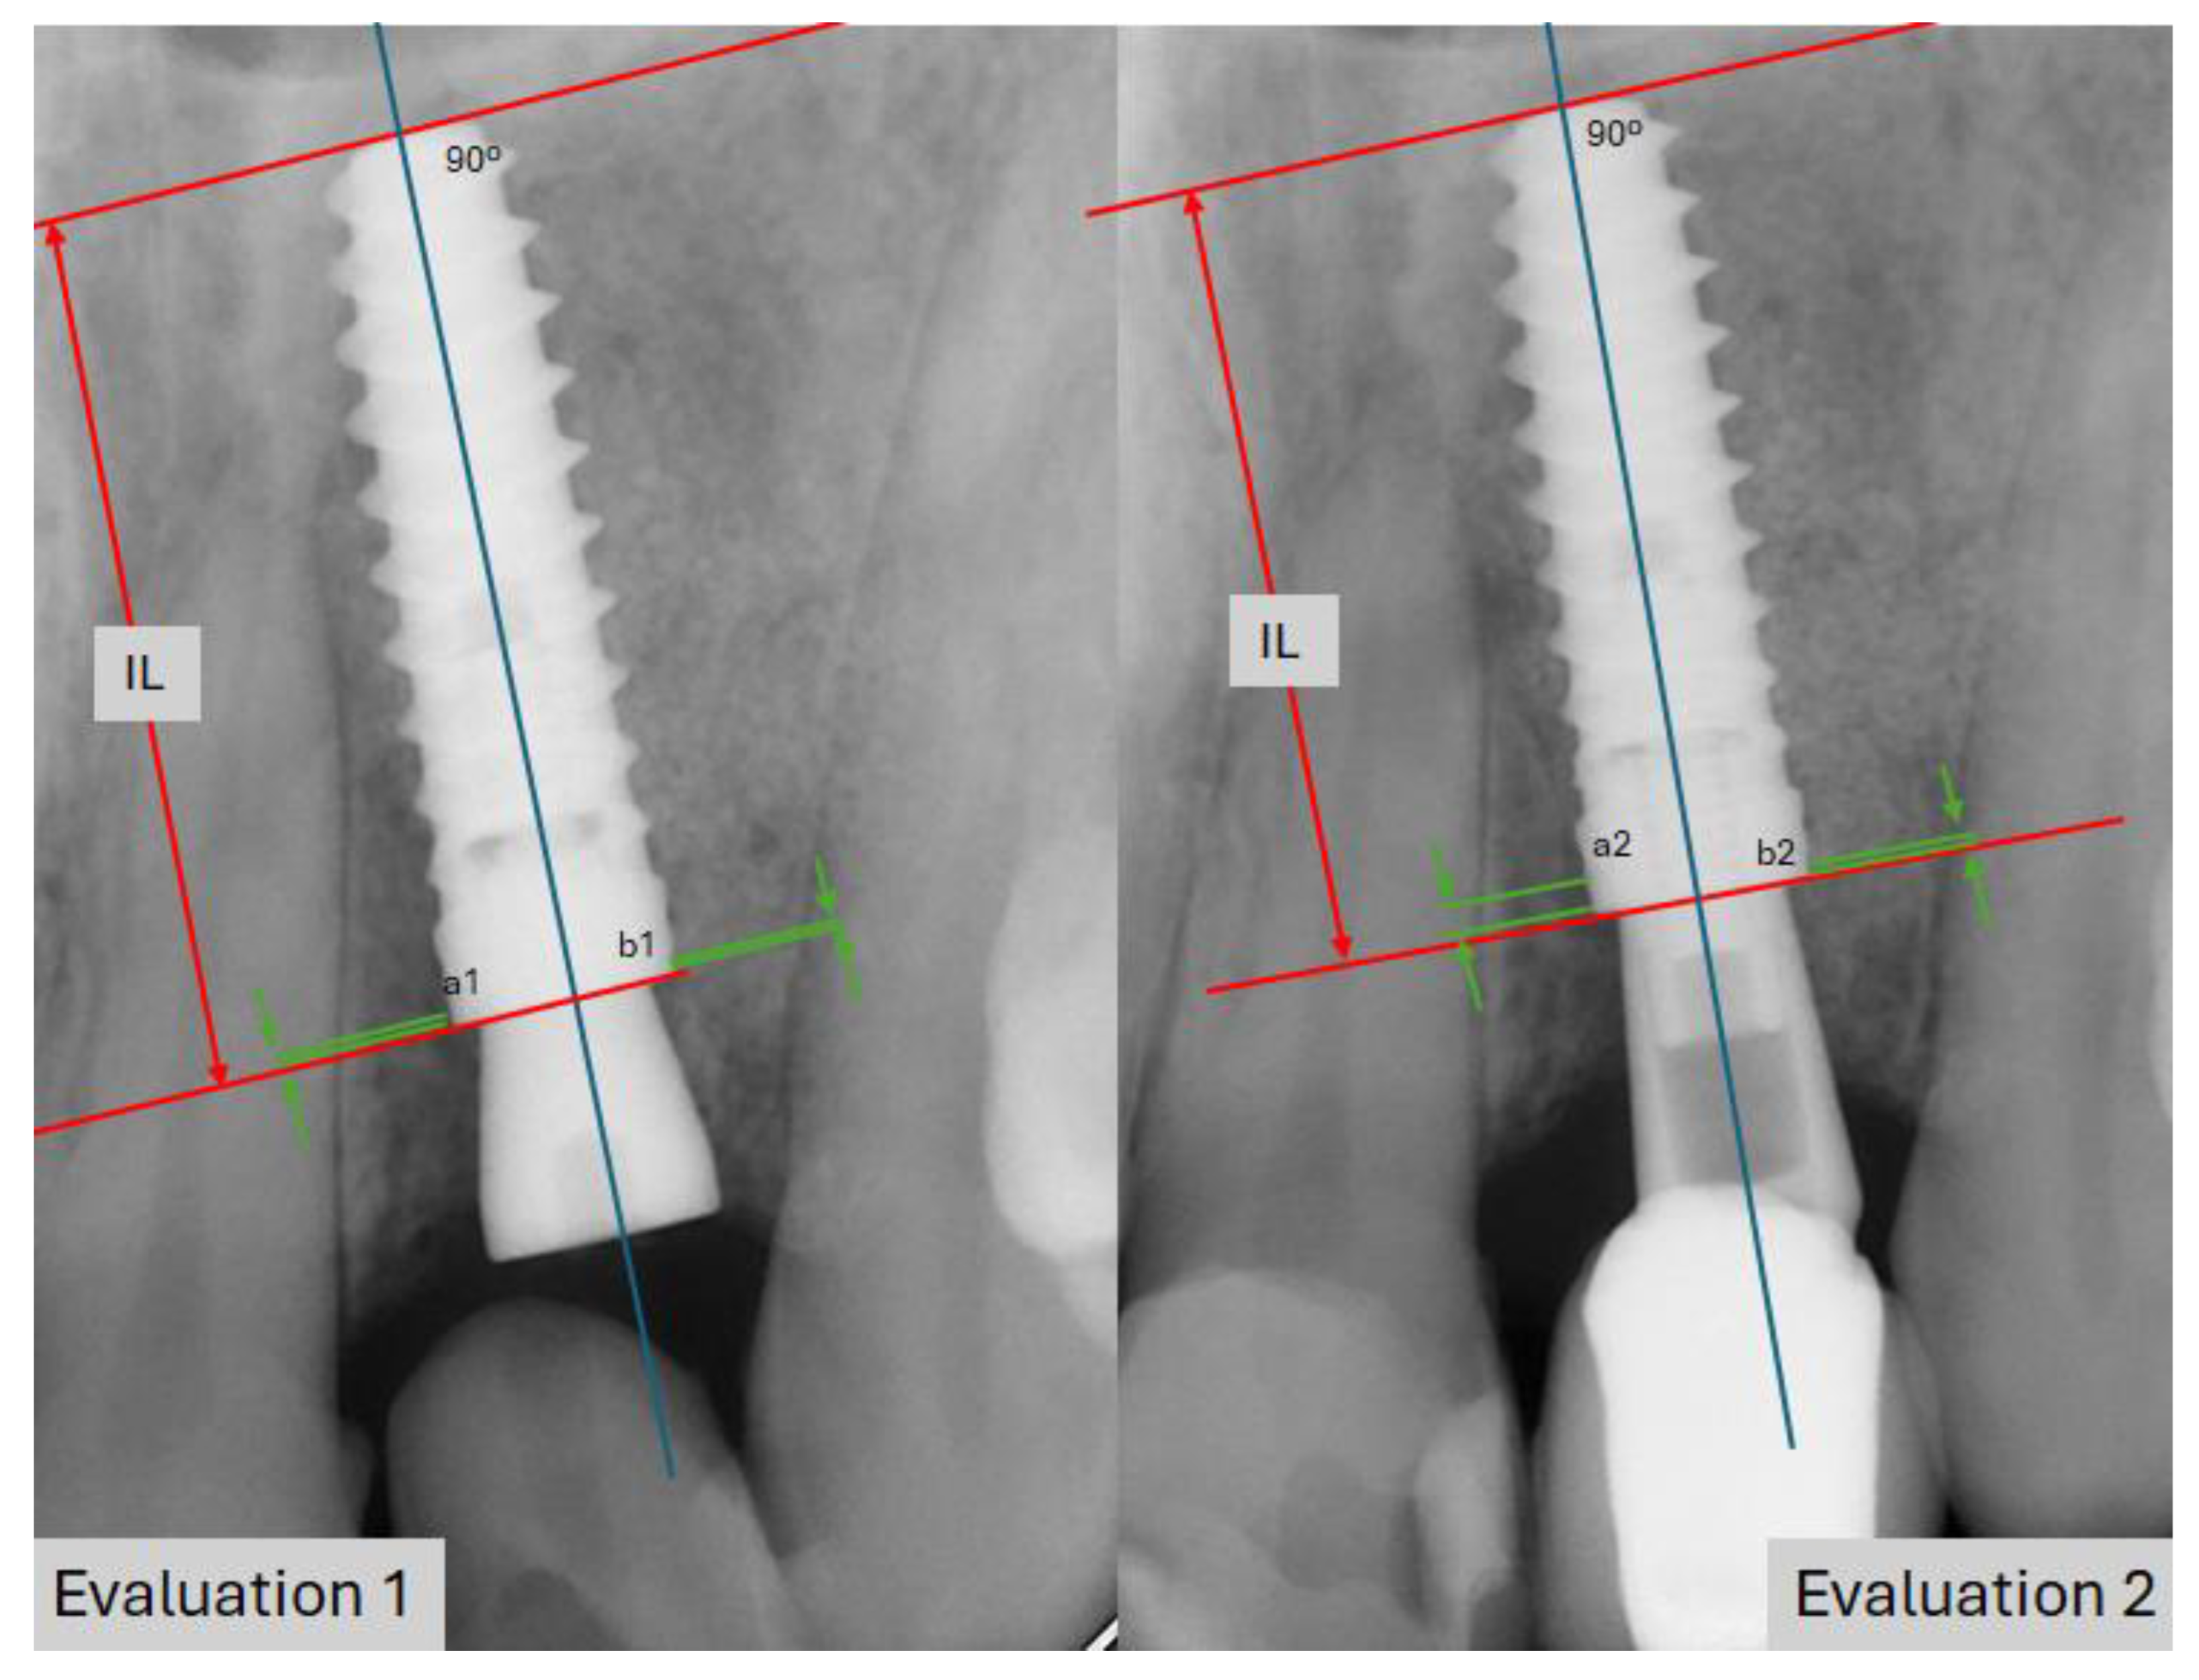

Follow-up appointments took place at 3 and 6 months after prosthesis placement and annually thereafter, with a follow-up duration of 140.6 months on average (ranging from 120 to 148 months). Implant success was determined by its stability, along with the absence of radiolucent areas around the implant, signs of mucosal suppuration, or any associated discomfort. Marginal bone loss was measured through intraoral digital radiographs captured at a right angle to the implant’s long axis. To assess the marginal bone loss, both mesial and distal, we used the diagram shown in Figure 4. This analysis was conducted using orthopantomography and/or periapical radiographs. The length of the implant served as a reference, and measurements were taken under standardized lighting conditions using 20× magnification loupes (RS PRO Magnifier, 20× magnification, lens Ø30 mm, RS Code: 732-858, RS-PRO, Barcelona, Spain).

Figure 4.

Diagram illustrating the method used to calculate mesial and distal marginal bone loss. IL: implant length. The red arrow indicates the known implant length, while the green arrows reference the crestal bone and marginal bone loss, enabling comparison at different times in this study. a1: distal bone level in evaluation 1; a2: mesial bone level in evaluation 2; b1: distal bone level in evaluation 1; b2: mesial bone level in evaluation 2.

As an example, marginal bone loss at point a2, relative to point a1, is calculated by analyzing the distortion of the implant in Evaluation 2 compared to Evaluation 1: IL2/real IL = x; IL1/real IL = y. By dividing x-y by the real IL, we determine the distortion (positive or negative) between the two radiographs. This percentage is then multiplied by a2-a1 to obtain an adjusted measurement of bone loss.